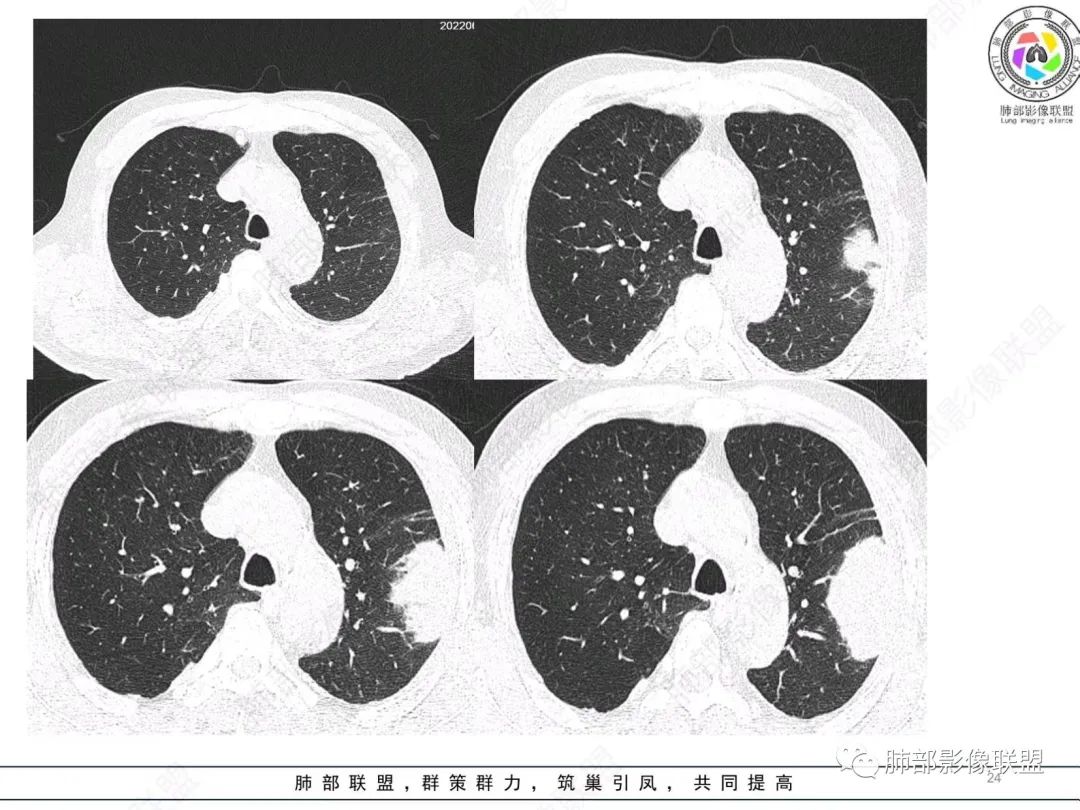

左肺上叶大肿块,膨胀性生长,边界清,密度较低,见部分坏死区,强化弱,肿块见支气管充气V扩张征,分布僵直,枯树枝特点,另一个重要特点血管造影征,淋巴瘤,肿块长轴与胸膜平行,与隐球菌鉴别,隐球荚膜抗原检查,明确诊断经皮肺穿刺。另胸膜钙化(问诊既往有无患胸膜炎病史)。

左肺上叶胸膜下肿块,宽基底与胸膜相连,跨叶裂,边缘清晰膨隆,其内支气管充气,部分扩张、僵直,无明显强化,血管造影征,考虑淋巴瘤,鉴别腺癌

左肺胸膜下巨大占位,跨叶裂,宽基底与胸膜相连,胸膜钙化,平扫密度较低,强化不明显,可见内部血管显影,支气管充气征和扩张,考虑为恶性,倾向于淋巴瘤

左肺上叶胸膜下肿块,膨胀性生长,边界清晰,密度不均部分坏死,未见强化,病灶内支气管迂曲扩张,病灶长轴与胸膜平行,胸膜下脂肪间隙存在,胸膜钙化,考虑放线菌?毛霉?鉴别淋巴瘤

左肺上叶肿块,宽基底与胸膜相连,跨叶裂,边缘清晰膨隆,可见小分叶,其内支气管充气,部分扩张、僵直,呈枯枝征,支气管达边征,增强无明显强化,可见血管造影征,考虑恶性病变,淋巴瘤,鉴别粘液腺癌。

大肿块,边缘光滑,深分叶

近端支气管堵塞、推移为主

内部支气管扩张

1)部位:周围型或中央型软组织肿块,以周围型为多见,且肿瘤多位于肺上叶。如本例:该肿瘤位于左肺上叶。

3)肿块边界和边缘:多较清楚,呈圆形、类圆形,且由于肿块生长速度不均匀,可见分叶,毛刺少见。有报道肿块周围毛玻璃影是多形性癌特征表现。